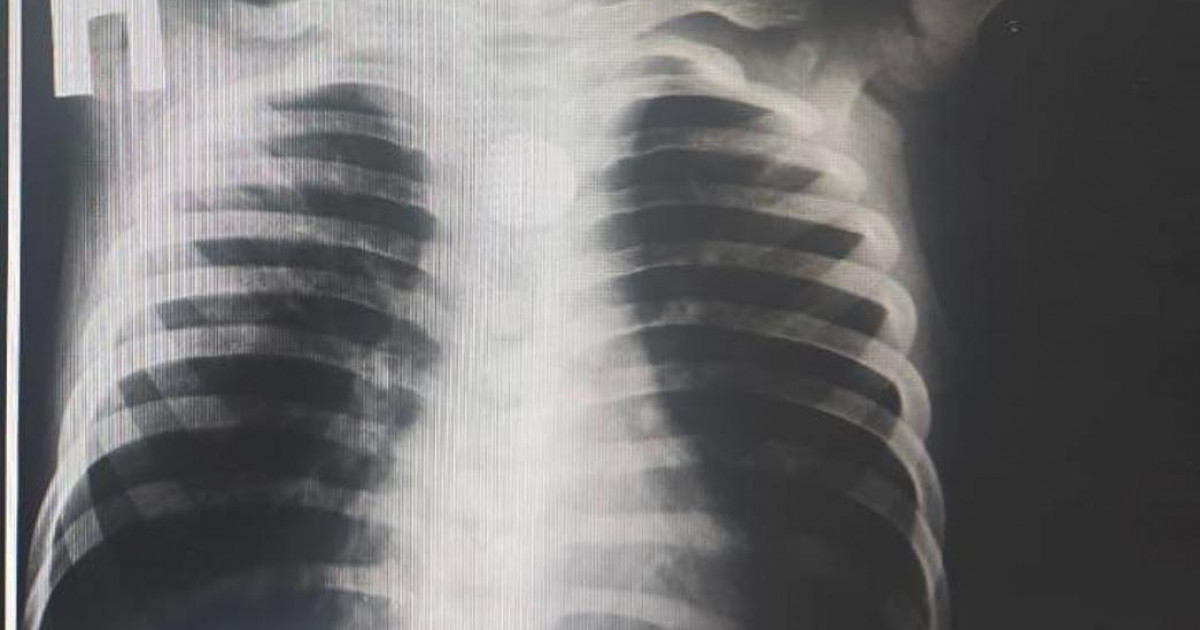

Әлем халқы апта басында туберкулез ауруына қарсы күрес күнін атап өтті. Бұл іс-шара 1982 жылы Дүниежүзілік денсаулық сақтау ұйымы мен Туберкулез және өкпе ауруларымен күрес жөніндегі халықаралық одақтың (International Union against Tuberculosis and Lung D...

Қазақстан туберкулезді жою жөніндегі жаһандық стратегияны ұстанады, сырқаттанушылық 13%–ға, өлім 25%-ға төмендеді.